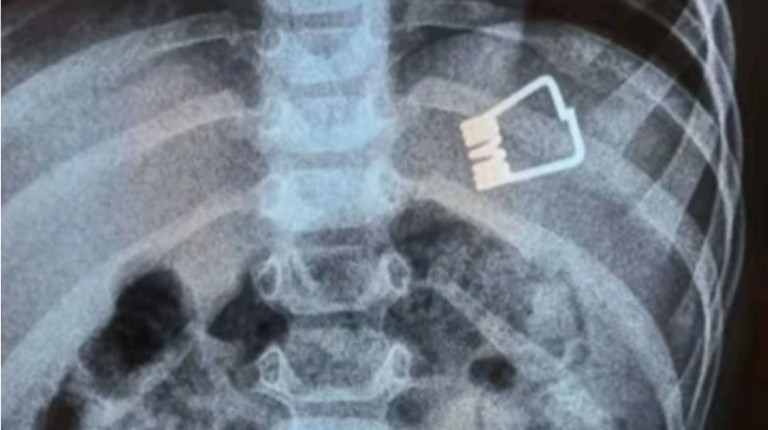

Το παιδί επέστρεψε στη Λήμνο και είναι καλά στην υγεία του